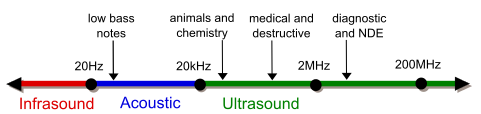

Indulge in the remarkable luxury of our ultrasound vs x-ray-difference between ultrasound and x-ray collection with extensive collections of exquisite images. showcasing the grandeur of music, song, and instrument. perfect for high-end marketing and branding. The ultrasound vs x-ray-difference between ultrasound and x-ray collection maintains consistent quality standards across all images. Suitable for various applications including web design, social media, personal projects, and digital content creation All ultrasound vs x-ray-difference between ultrasound and x-ray images are available in high resolution with professional-grade quality, optimized for both digital and print applications, and include comprehensive metadata for easy organization and usage. Our ultrasound vs x-ray-difference between ultrasound and x-ray gallery offers diverse visual resources to bring your ideas to life. Each image in our ultrasound vs x-ray-difference between ultrasound and x-ray gallery undergoes rigorous quality assessment before inclusion. Advanced search capabilities make finding the perfect ultrasound vs x-ray-difference between ultrasound and x-ray image effortless and efficient. Comprehensive tagging systems facilitate quick discovery of relevant ultrasound vs x-ray-difference between ultrasound and x-ray content. Our ultrasound vs x-ray-difference between ultrasound and x-ray database continuously expands with fresh, relevant content from skilled photographers. Whether for commercial projects or personal use, our ultrasound vs x-ray-difference between ultrasound and x-ray collection delivers consistent excellence.